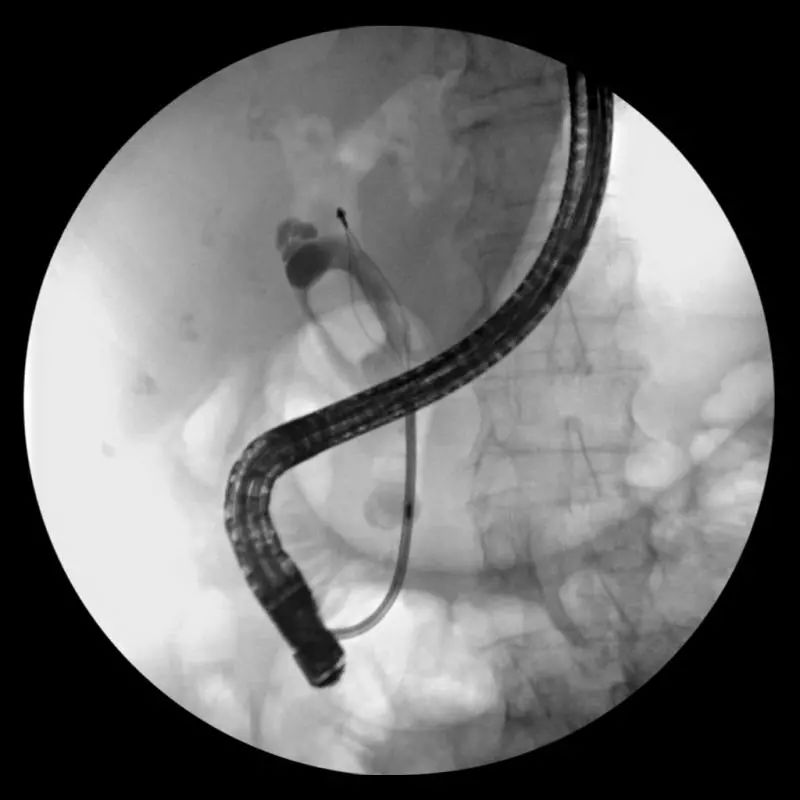

周老太被收住肝胆外科病房,追问病史,完善检查后了解到,老太太合并有高血压、冠心病等多种基础疾病,平时口服阿司匹林等多种药物,且磁共振检查(MRCP)提示目前胆管内的结石已经增大到约2.5cm大小,堵塞了胆管下端,普通人的胆总管正常直径是3-8mm,而周老太的胆管直径已经扩张到正常的3-4倍。若不处理结石,解除胆道梗阻,病情也难以彻底好转,周老太还是要在鬼门关前晃悠。而要处理结石,则要冒着巨大的风险,克服重重技术困难。为挽救病人生命,肝胆外科医生当机立断,在告知患者家属病情并取得同意后,决定采用内镜微创,也就是内镜逆行胰胆管造影(ERCP)的方式解除梗阻。周老太被送入内镜中心,麻醉成功后,医生通过十二指肠镜,将导丝通过十二指肠乳头(即胆总管的下端开口处)置入胆管内,并用高频电刀将乳头部分切开,再用球囊将开口处撑开使得胆汁能顺畅流出;而因结石巨大,无法直接将其取出,采用了先用碎石网篮将结石夹碎后,再用取石网篮分次取出的方式,将周老太胆管内的结石全部取出。术后第一天周老太症状就明显缓解,恢复流质饮食,术后3天就痊愈出院了。

内镜逆行胰胆管造影(ERCP)示意图